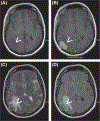

Fig. 1.

MR imaging shows a new, lobulated, extra-axial, duralbased mass in the right posterior parietal area. The lesion is seen as isointense to gray matter on T1-weighted sequences (A) with avid, homogeneous contrast enhancement (B) and isointense on T2-weighted (C) and fluid-attenuated inversion recovery sequences (D).